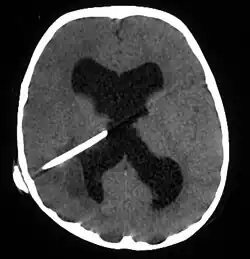

The diagnosis is established by a computed tomography (CT) (with contrast) examination. At the initial phase of the inflammation (which is referred to as cerebritis), the immature lesion does not have a capsule and it may be difficult to distinguish it from other space-occupying lesions or infarcts of the brain. Within 4–5 days the inflammation and the concomitant dead brain tissue are surrounded with a capsule, which gives the lesion the famous ring-enhancing lesion appearance on CT examination with contrast (since intravenously applied contrast material can not pass through the capsule, it is collected around the lesion and looks as a ring surrounding the relatively dark lesion). Lumbar puncture procedure, which is performed in many infectious disorders of the central nervous system is contraindicated in this condition (as it is in all space-occupying lesions of the brain) because removing a certain portion of the cerebrospinal fluid may alter the concrete intracranial pressure balances and causes the brain tissue to move across structures within the skull (brain herniation).[14]

Ring enhancement may also be observed in cerebral hemorrhages (bleeding) and some brain tumors. However, in the presence of the rapidly progressive course with fever, focal neurologic findings (hemiparesis, aphasia etc.) and signs of increased intracranial pressure, the most likely diagnosis should be the brain abscess.[15]